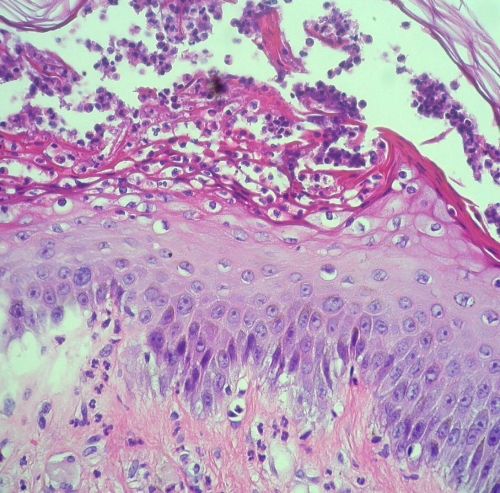

Exanthematous pustulosis = البثار الطفحي